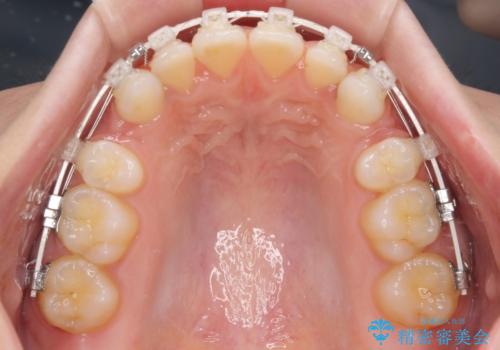

- 矯正装置

- 審美装置

- 前歯のデコボコとクロスバイトを気にして来院された患者様です。

上下ともにデコボコはそれほど強くありませんでしたが、非抜歯では口元が突出した仕上がりとなる可能性があるため、上下左右の第一小臼歯4本を抜歯し、ワイヤー装置での抜歯矯正を行うこととしました